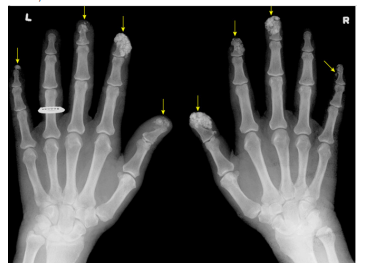

A imagem seguinte apresenta extensa calcificação

envolvendo os tecidos moles das falanges distais de ambas as

mãos, chamada de calcinose cutânea:

Fonte: UpToDate, 2023.

A calcinose cutânea está geralmente associada: